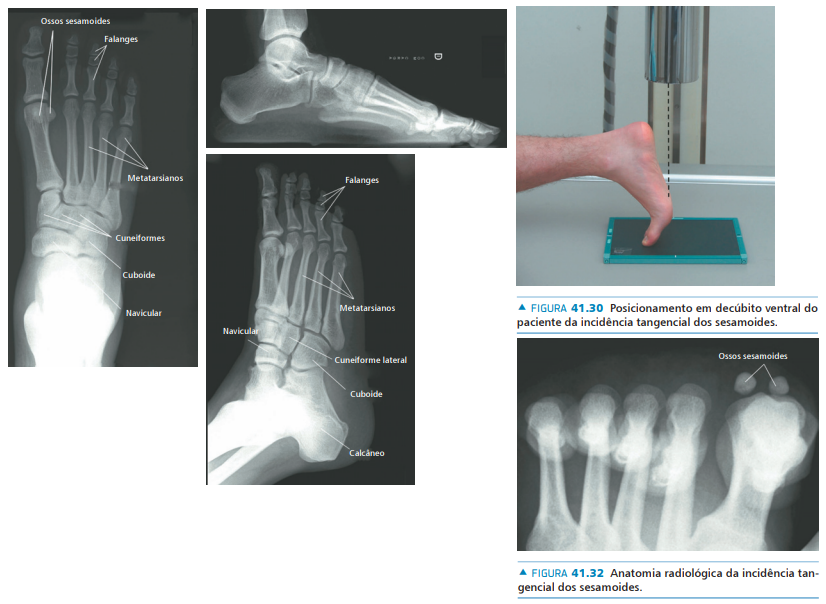

• Anatomia da superfície plantar da cabeça do 1° metatarso:

• Na avaliação radiográfica, quais incidências solicitar?

A

• AP com carga

• Perfil com carga

• Oblíqua

• Axial dos sesamóides

• Na avaliação radiográfica em AP com carga, quais os principais ângulos a serem traçados?

• Ângulo de valgismo do hálux (metatarsofalângico)

• Ângulo intermetatarsal

• Ângulo de valgismo interfalângico do hálux

• Ângulo articular metatarsal distal (AAMD)